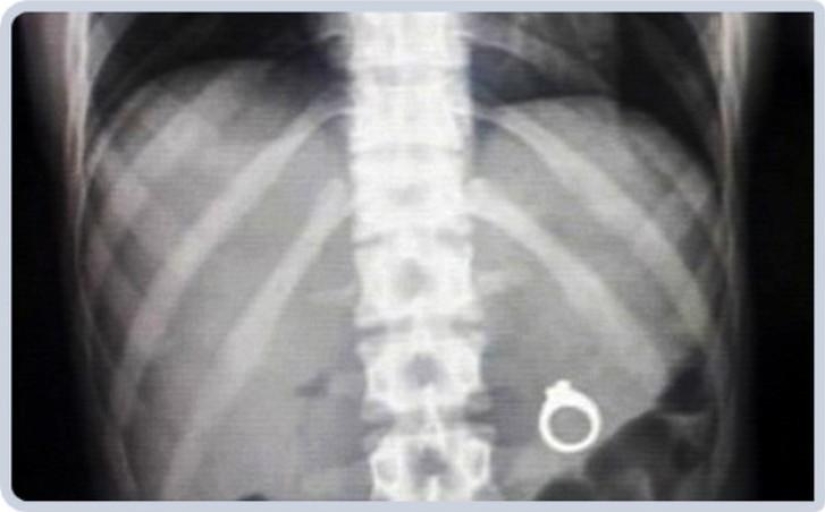

3. Anillo de bodas.